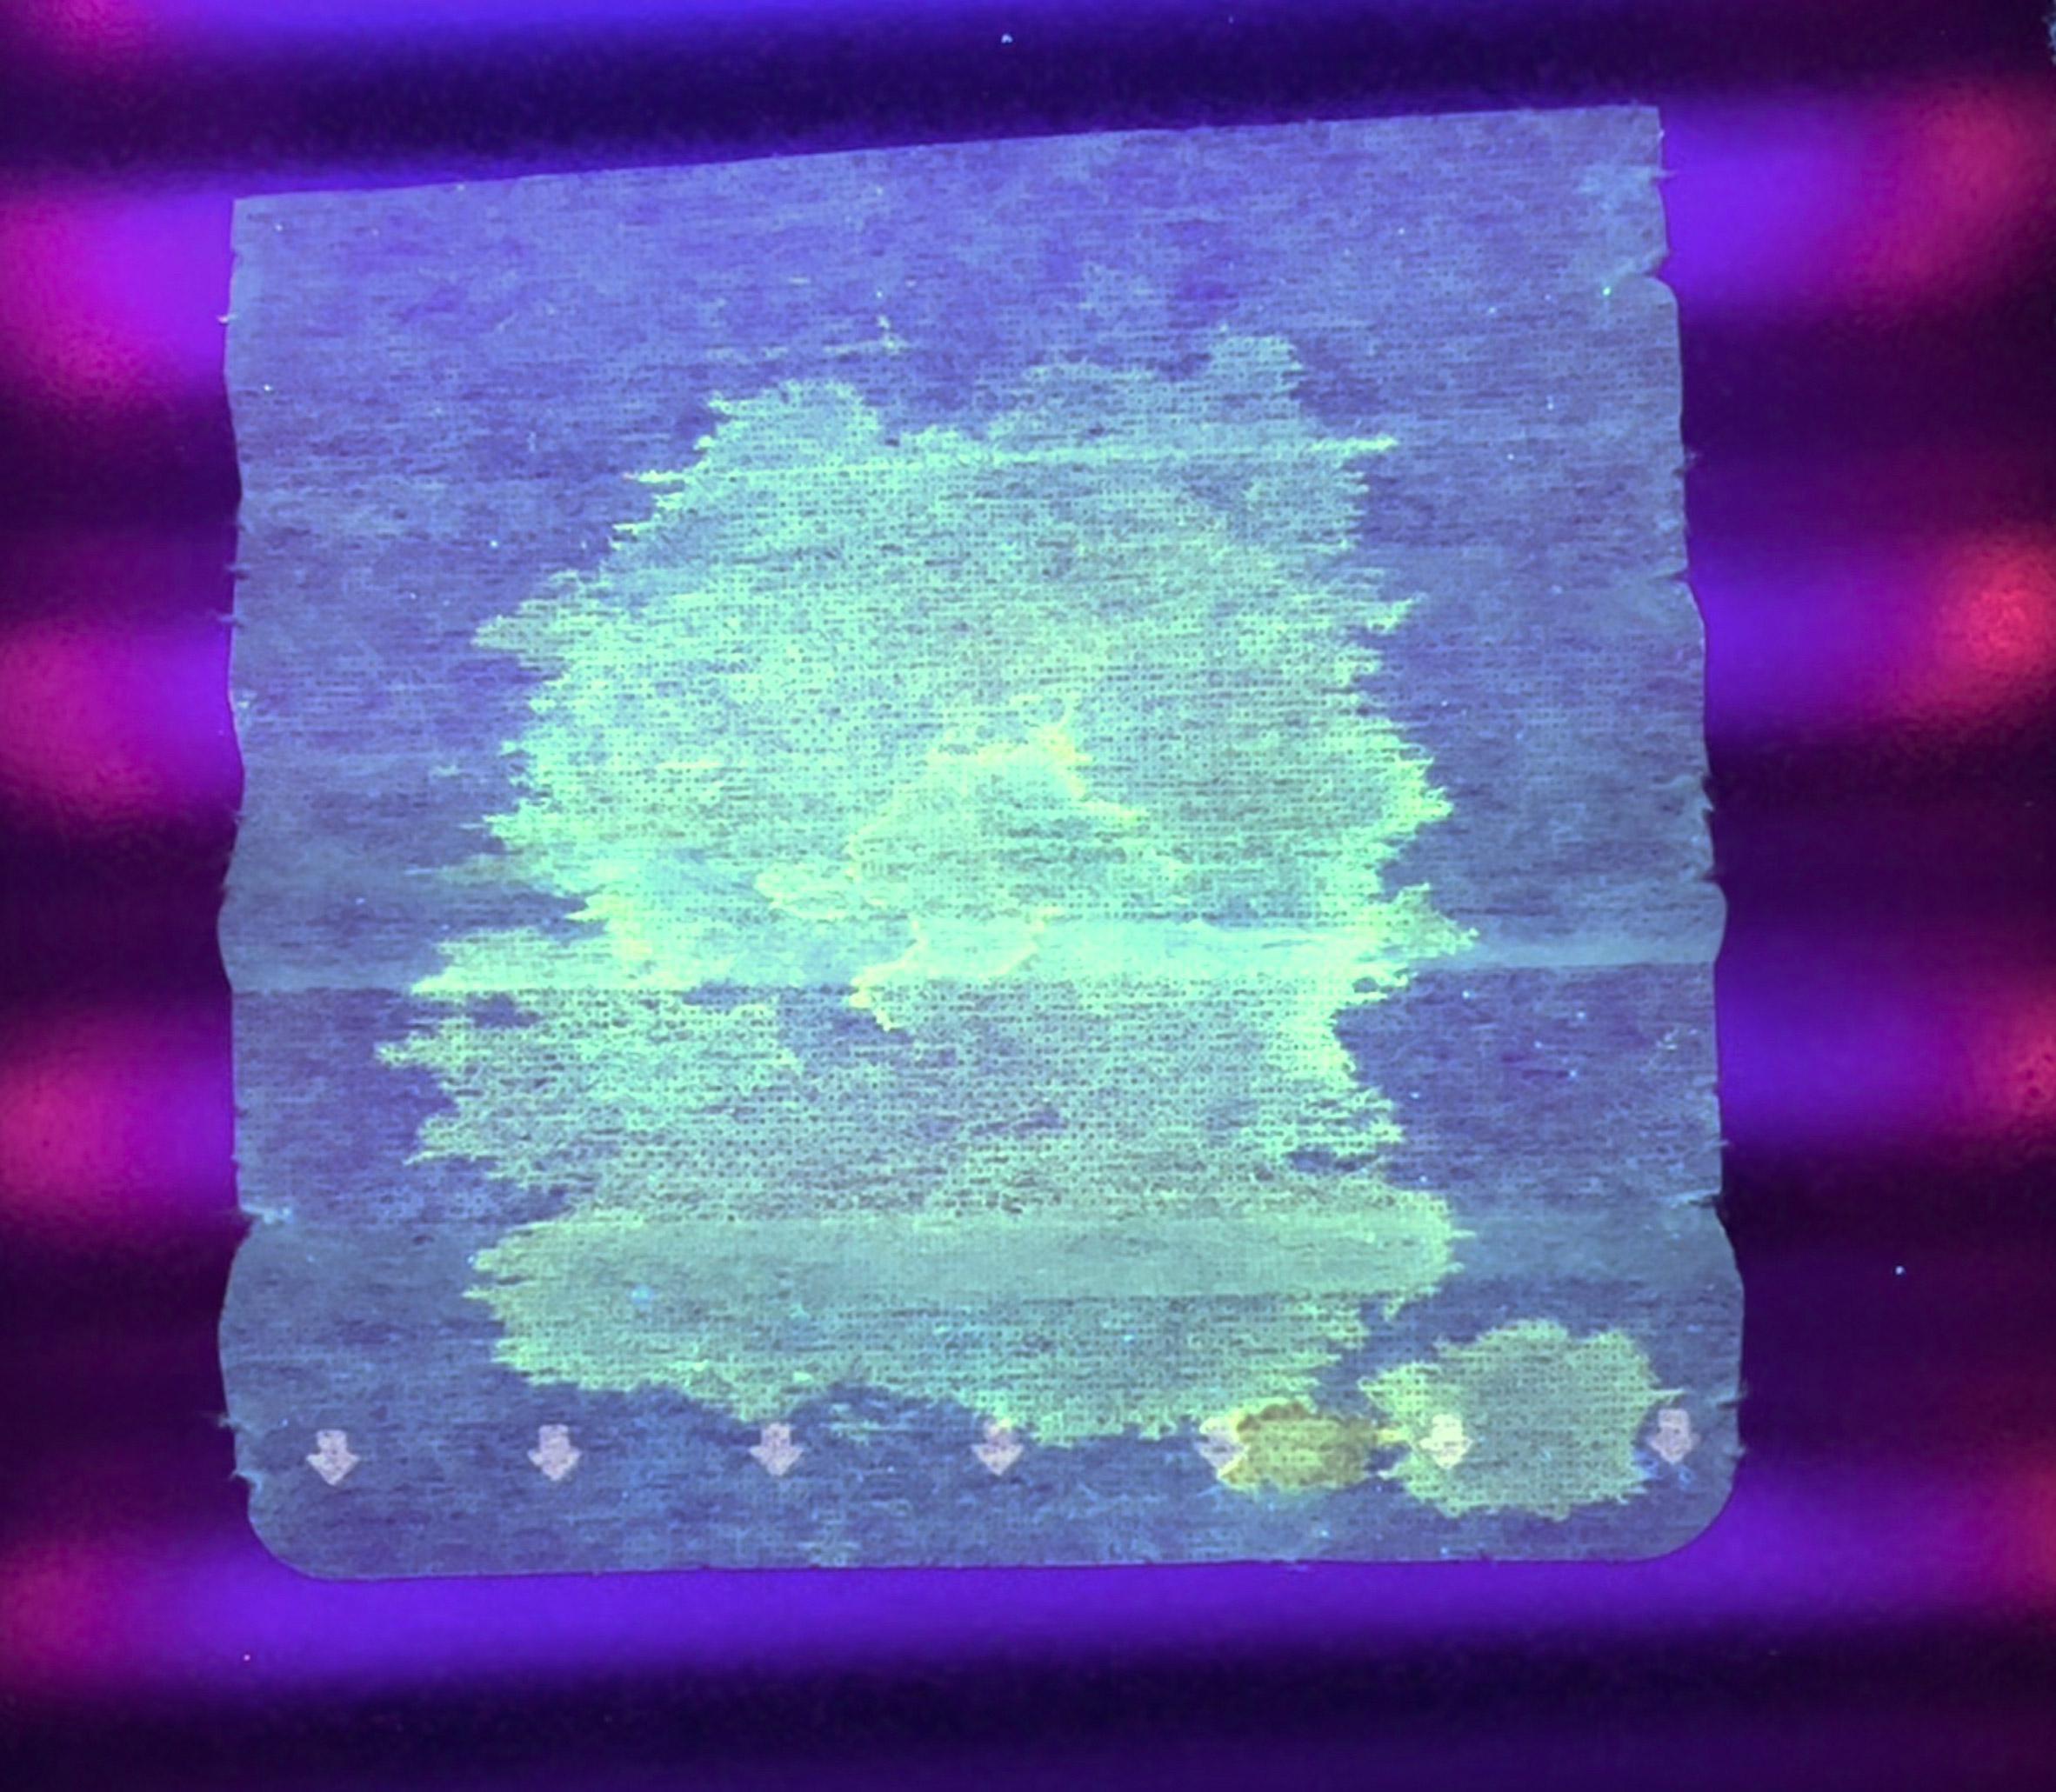

პირბადეში მოთავსებულია სპეციალური ფილტრი, რომელიც კორონავირუსის დაფიქსირების შემთხვევაში ანათებს. უკვე ჩატარდა შესაბამისი კვლევები და ახალი გამოგონების ეფექტიანობა მათ შედეგად უკვე დადასტურებულია.

"სირაქლემები თავიანთი ძლიერი იმუნური სისტემის გამო, უაღრესად მდგრადები არიან კორონავირუსის მიმართ. ამან მიბიძგა მათი ანტისხეულების გამოკვლევა დამეწყო. თუ ერთჯერადი ნიღბის ქვეშ სირაქლემას ანტისხეულებიან ფილტრს გამოვიყენებთ, იმ ადამიანებს, რომლებიც ასიმპტომურები არიან, მაგრამ ვირუსს აქტიურად ავრცელებენ, ადრეულ სტადიაზევე ვუმკურნალებთ", - ამბობს ის.

მკვლევარს იმედი აქვს, რომ მსგავსი ტექნიკის საშუალებით, სხვა ვირუსებისგანაც მოვახერხებთ თავის დაცვას. ჯერჯერობით, სირაქლემას ანტისხეულებიანი ფილტრები მხოლოდ ულტრაიისფერი გამოსხივების ფონზე ანათებენ.